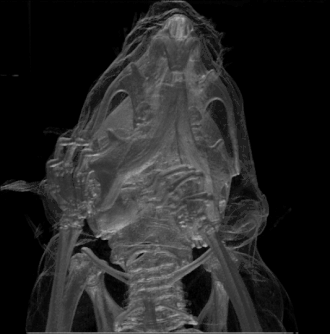

Computed tomography (CT) and positron emission tomography (PET) scans are similar to MRI, but rely on different imaging techniques (X-rays and ionizing radiation, respectively). A variation of CT known as contrast CT also requires the subject to take in a contrast medium called a radiocontrast (typically by oral consumption, enema, or injection). Positive radiocontrast agents such as barium sulfate increase the body's X-ray attenuation, causing the tissue containing them to appear whiter in the X-ray image. Meanwhile, negative agents such as carbon dioxide gas allow X-rays to pass through them easily, causing the tissues containing them to appear darker.[49]

Like magnetic resonance imaging, CT scans use numerous methods to display and measure data, including sequential CT (where the CT table steps from location to location), spiral CT (where the entire X-ray tube is spun around the subject), and electron beam tomography (where only the electron paths are spun using deflection coils). PET scanners don’t have quite as much hardware variation and instead use different radiotracers depending on what the imaging target is. Note that radiotracers are distinct from radiocontrasts; the former relies on radioactive decay to trace its path while the latter is absorbed into specific tissue and affects that tissue's X-ray attenuation. Because these methods are not mutually exclusive, PET and CT can be performed simultaneously using PET-CT scanners, which are used for the majority of modern PET scans.[50]

Either or both of these methods can be used in conjunction with maximum intensity projection (MIP) to convert the scan data into a 3D image. This can be difficult to accomplish due to artifacts created by respiration and bloodflow, which can appear as abnormalities to an untrained eye; however, it's possible to distinguish these artifacts from real disease so long as careful attention is paid to them.[51] When done well, CT and PET scans taken with MIP are excellent for identifying small abnormal tissue growths, especially in the lungs. Scans taken with MIP for this purpose tend to have higher significance than averaged images created with traditional CT.[52]

MIP imaging is also used with magnetic resonance angiography, and research has indicated that it could feasibly be used with MRI.[53] At least one study has shown that MIP MRI actually significantly outperforms single-slice MRI when used by neural networks to classify lesions based on malignancy.[54]